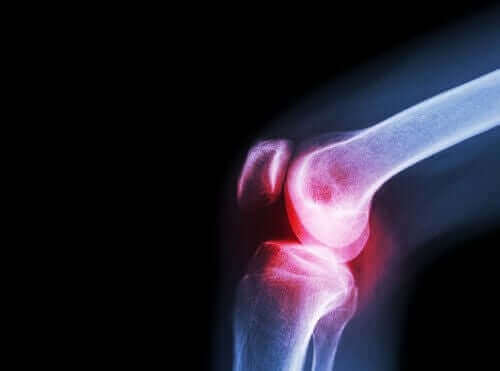

Reumatoïde artritis is een chronische inflammatoire auto-immuunziekte. Deze ziekte treft meerdere gewrichten en heeft verschillende algemene en niet-specifieke symptomen.

Wat betreft de symptomen manifesteert reumatoïde artritis zich meestal met pijn en stijfheid, en ook moeite met het bewegen van verschillende kleine en grote gewrichten.

Het meest voorkomende symptoom is echter ochtendstijfheid, vooral in de voeten en handen. De triggers van reumatoïde artritis zijn nog onbekend. Zoals we hierboven al vermeldden, weten we echter dat het een auto-immuunziekte is en dat andere oorzaken en genetische en niet-genetische factoren tot de manifestatie ervan leiden.

Artsen bevelen aceclofenac ook voor deze aandoening aan. Artrose is namelijk een andere reumatische aandoening die het gewrichtskraakbeen beschadigt.

De gewrichten bevatten een vloeistof bekend als gewrichtsvloeistof dat door het gewrichtsmembraan geproduceerd wordt. De uiteinden van de botten die samenkomen om een gewricht te vormen, zijn met gewrichtskraakbeen bedekt.

Wanneer dit kraakbeen schade ondervindt, dan veroorzaakt het pijn, stijfheid en functionele beperkingen. Het is daarom belangrijk om deze ziekte van artritis te onderscheiden. De laatste ontwikkelt zich als gevolg van gewrichtsontsteking en niet door kraakbeenslijtage.